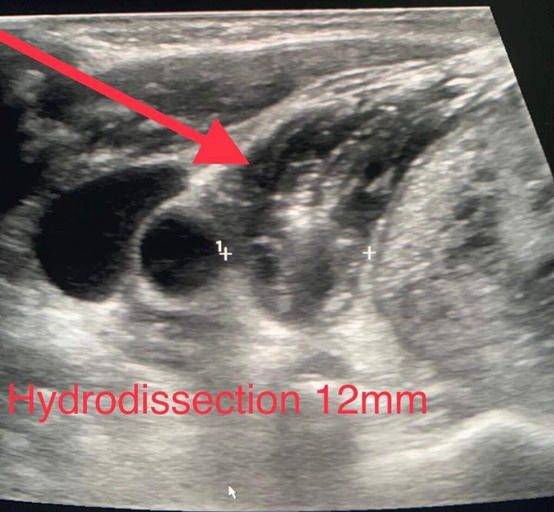

وبين أخصائي الأشعة التشخيصية والتصوير التلفزيوني التداخلي الرائد الطبيب محمد حمدي الحياري، أن العملية أجريت تحت التخدير الموضعي فقط وتحت توجيه جهاز التصوير التلفزيوني بتقنية الكي (microwave ablation) في وقت بلغ ٢٥-٣٠ دقيقة دون مضاعفات وغادر المريض المستشفى في نفس اليوم، مشيرا لأن هذا النوع من العمليات يتميز بقلة المضاعفات مقارنة بالعمليات الجراحية التقليدية و لا يترك أي ندب جراحية.